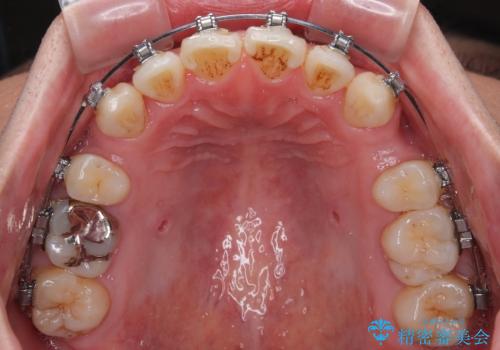

- 矯正装置

- メタルブラケット

- 口元の突出感が強く、口が閉じにくいことを主訴として来院された患者さんの症例をご紹介します。

前歯部の叢生(デコボコ)も認められ、歯がきれいに並ぶためのスペースが不足している状態でした。

これらの問題を総合的に改善するため、上下左右の第一小臼歯を計4本抜歯し、スペースを確保する治療計画を立てました。

抜歯したスペースを活用して前歯を後ろへ下げることで、口元の突出感を大きく改善。

奥歯の噛み合わせがずれている「シザーズバイト」を適正に整えることで、見た目だけでなく機能性も向上し、安定した咬合が獲得できました。

前歯のデコボコが整い、清掃性が向上